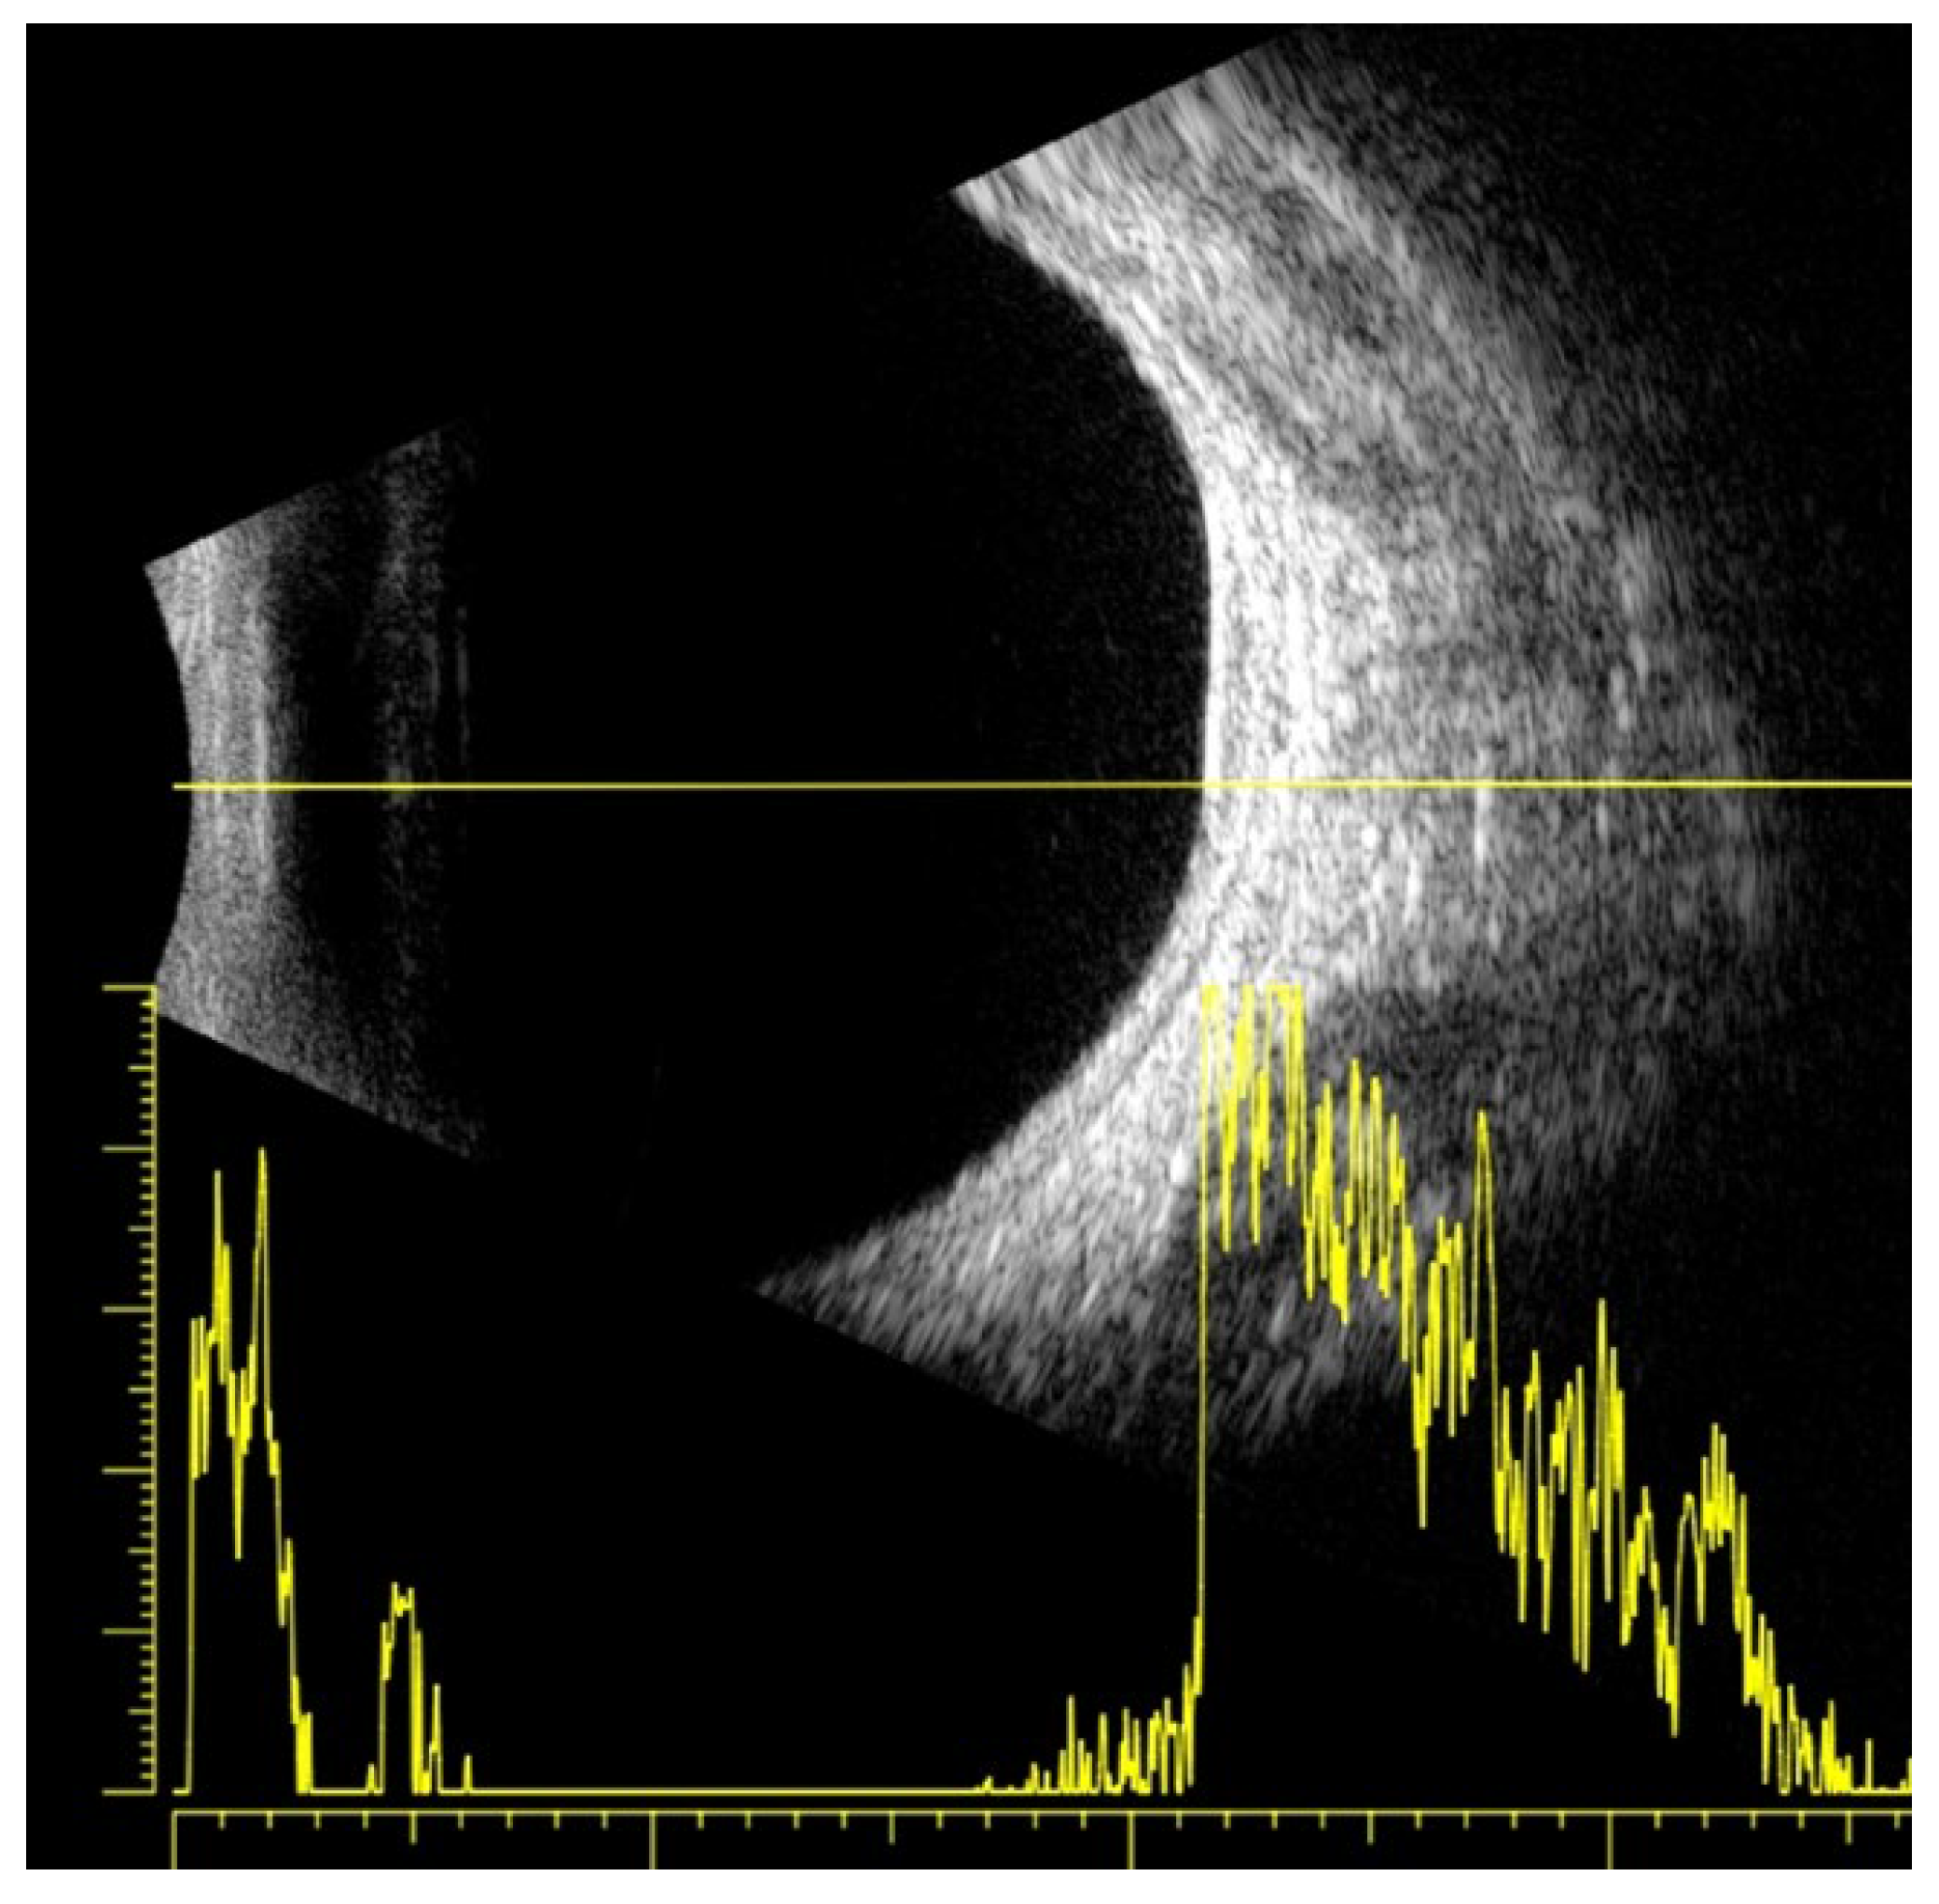

2.2. Clinical Findings

2.3. Diagnostic Assessment